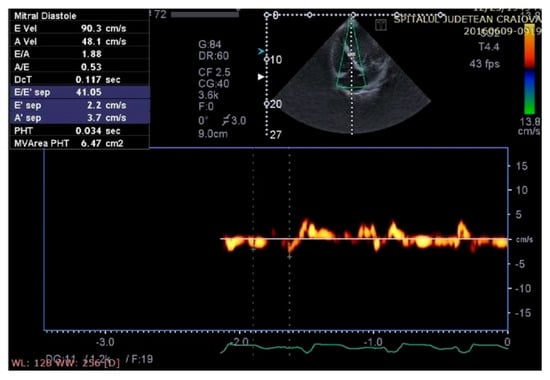

Figure 8.

Aspect of waveforms of tissue Doppler interrogation at the interventricular septum before therapy with a cardiac resynchronization device (yellow color).

Figure 9.

Aspect of waveforms of tissue Doppler interrogation at the interventricular septum after therapy with a cardiac resynchronization device (yellow color).